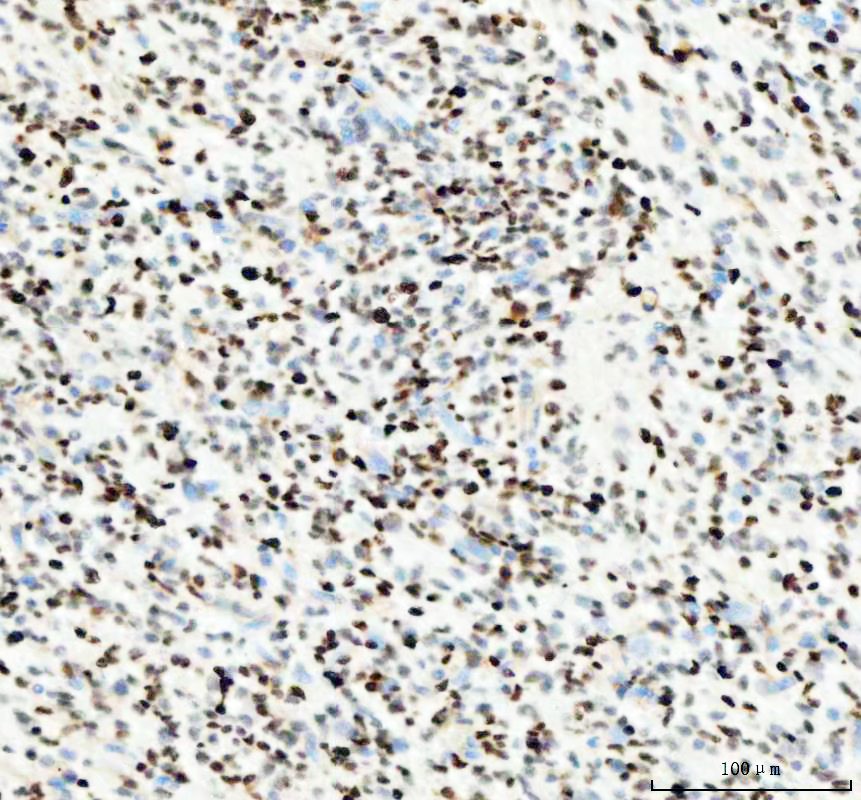

IHC analysis of PCNA using anti-PCNA antibody (A00125) .

PCNA was detected in a paraffin-embedded section of human tonsil tissue. The tissue section was incubated with rabbit anti-PCNA Antibody (A00125) at a dilution of 1:200 and developed using HRP Conjugated Rabbit IgG Super Vision Assay Kit (Catalog # SV0002) with DAB (Catalog # AR1027) as the chromogen.